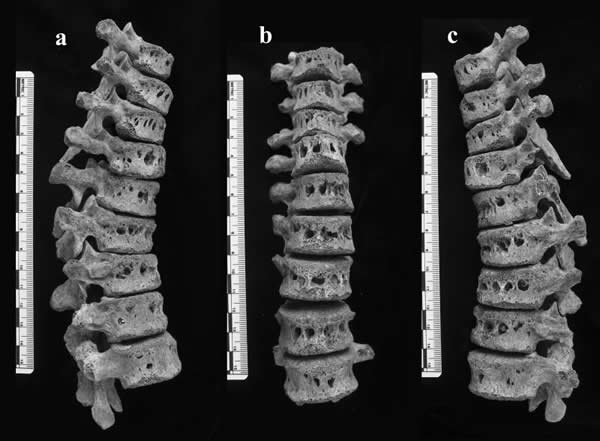

人类学家T. Fenton带领的研究组工作在阿尔巴尼亚,他们在对埋葬点挖掘出的人类遗骸建立生物学特征档案(包括性别、年龄、骨骼病理和健康史)的过程中发现了两个十世纪到十三世纪的青年男性身上的椎骨存在严重的损伤。他们猜想这两个男孩可能得了肺结核(tuberculosis),并将一些骨骼样本送到东兰辛的法医实验室。

Fenton的研究组于是重新检测了这些骨头,认为导致骨头损伤的可能是另一种病原菌——布氏杆菌。布氏杆菌病和肺结核病对骨头能造成相似的破坏——吃掉骨头,但还从没有人从考古点的人类骨骼中发现有布氏杆菌。